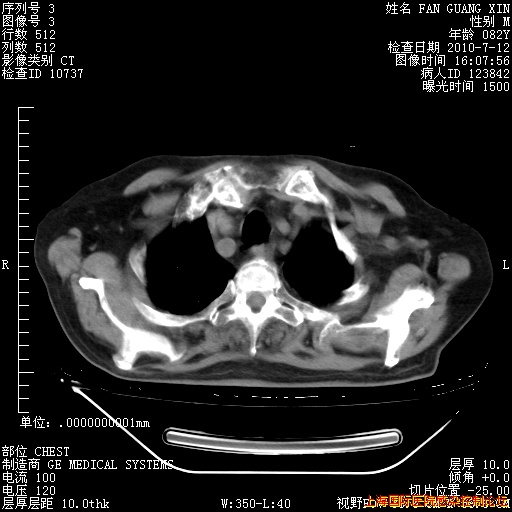

6月12日纵膈窗